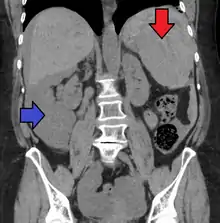

Splenic rupture is usually evaluated by FAST ultrasound of the abdomen.[4] Generally this is not specific to splenic injury; however, it is useful to determine the presence of free floating blood in the peritoneum.[4] A diagnostic peritoneal lavage, while not ideal, may be used to evaluate the presence of internal bleeding a person who is hemodynamically unstable.[5] The FAST exam typically serves to evaluate the need to perform a CT scan.[5] Computed tomography with IV contrast is the preferred imaging study as it can provide high quality images of the full peritoneal cavity.[4]